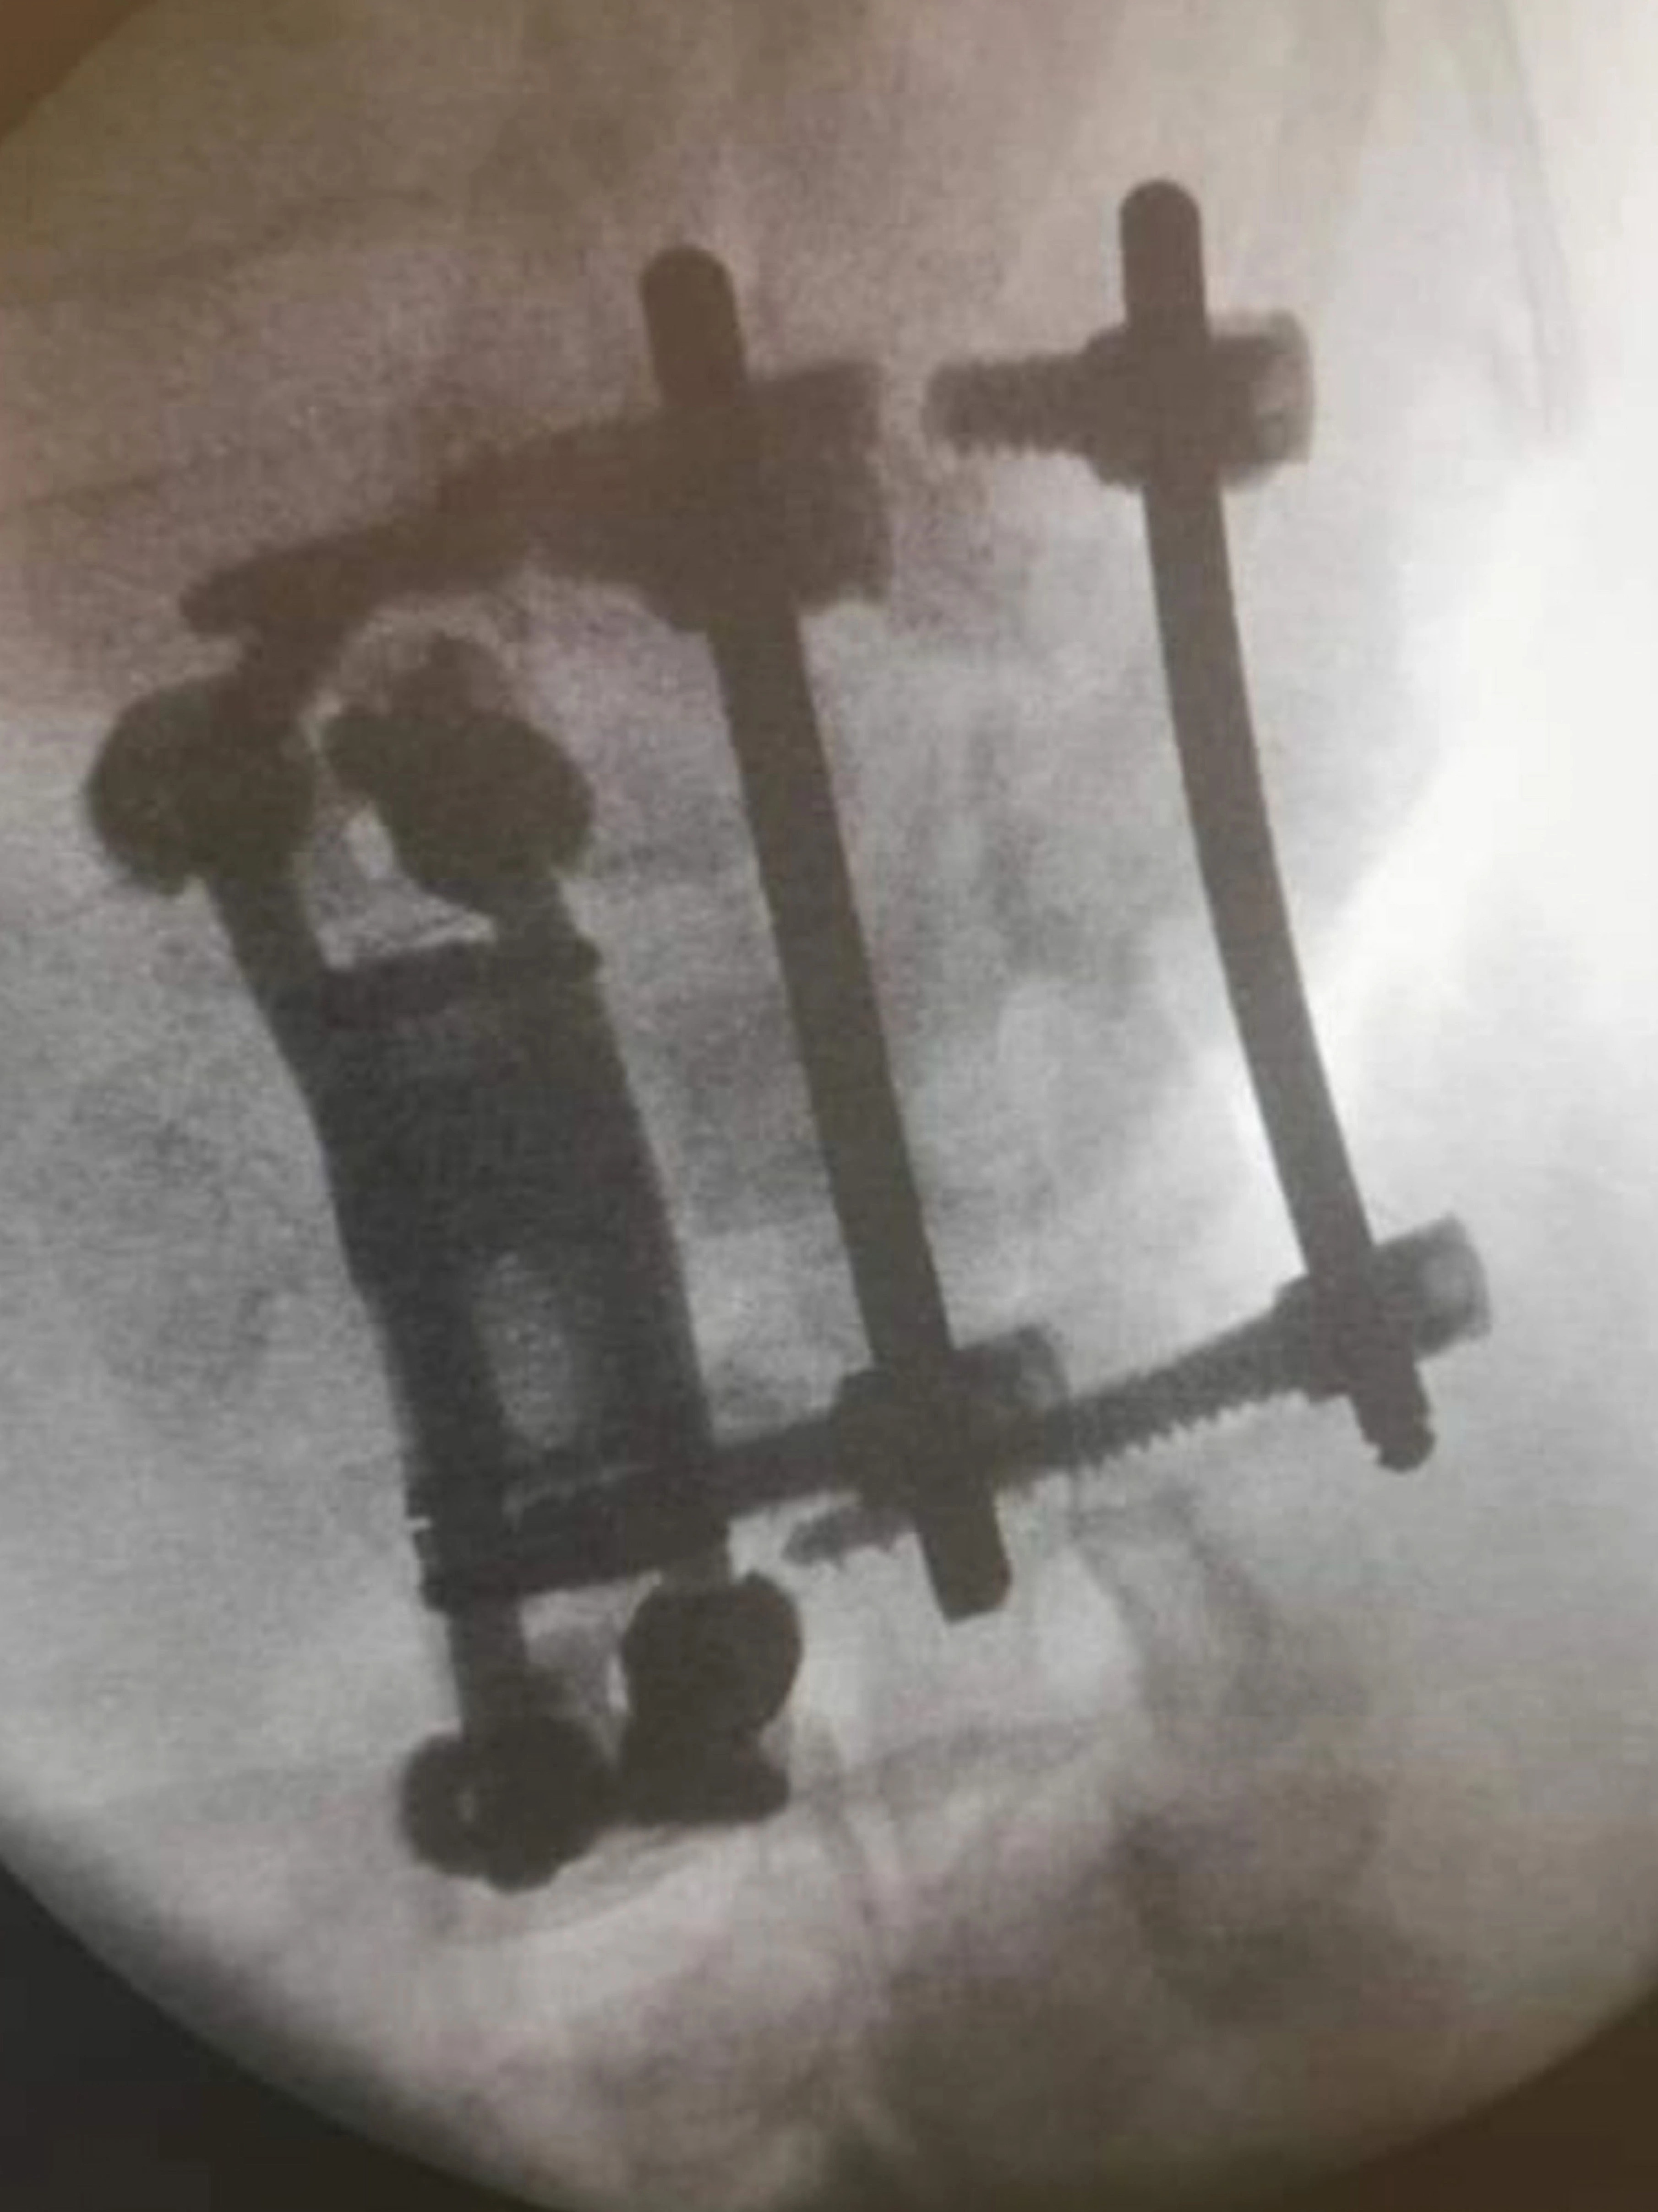

| Newman phải cắm một số thanh kim loại vào xương lưng. Ảnh: Mercury Press. |

Newman đã thực hiện phẫu thuật và phải gắn những thanh kim loại y tế vào lưng. Tuy nhiên, tổn thương ở dây thần kinh khiến chàng trai sinh năm 1993 mất cảm giác ở chân.